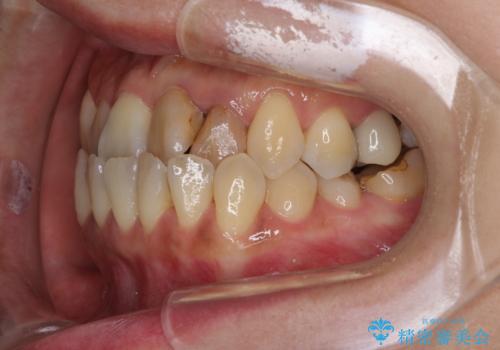

反対咬合で痛む前歯を改善 インビザラインによる矯正治療

- 前歯の反対咬合により、日々強い痛みを感じているとのことで来院された患者様です。

骨格的に下顎が前方位にありますが、歯列矯正で前歯の被蓋関係を改善することができると判断されたため、インビザラインにより矯正治療を行うこととしました。

前歯が内側に倒れ込む力がかかり、正常な歯ぎしりもできないため、非常に負担のかかりやすい咬み合わせでした。

矯正治療中に上顎前歯が下顎前歯を乗り越える際は、前歯でしか咬めない状況が続くため、食事など不便を感じましたが、治療後には前歯の痛みもなくなり、安定した咬み合わせとなりました。